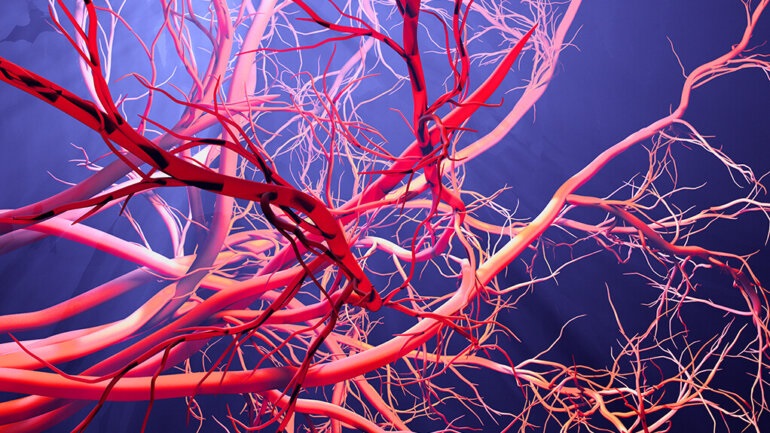

Κινήσου ενάντια στη θρόμβωση

Το μήνυμα «Κινήσου ενάντια στη θρόμβωση» ήταν το κεντρικό μήνυμα όλων των ομιλητών κατά τη διάρκεια Συνέντευξης Τύπου που οργάνωσε το Ι.Μ.Ε.Θ.Α., με αφορμή τον εορτασμό της Παγκόσμιας Ημέρας Θρόμβωσης (13 Οκτωβρίου). Ο εορτασμός της Παγκόσμιας Ημέρας Θρόμβωσης που φέτος κλείνει τα 10 χρόνια, έχει την επιστημονική αρωγή 19 Επιστημονικών Εταιρειών που σχετίζονται με τη […]